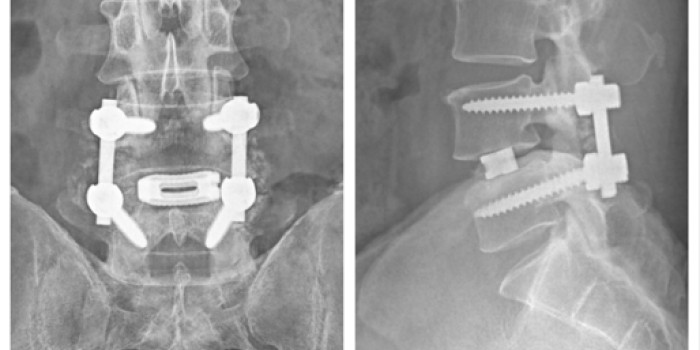

• Disc Herniation – Discectomy / Fusion Surgery

• Spinal Trauma – Fractures

• Revision Spine Surgery